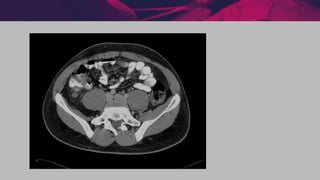

INVESTIGAÇÃO COMPLEMENTAR

Métodos de imagem

੦ tomografia computadorizada

• sensibilidade 87 a 100%

• especificidade 95 a 100%

• considerado o exame de maior confiabilidade

no diagnóstico de apendicite aguda

#IMPORTANTE INVESTIGAÇÃO COMPLEMENTAR Métodos deimagem ੦ tomografia computadorizada • sensibilidade 87 a 100% • especificidade 95 a 100% • considerado o exame de maior confiabilidade no diagnóstico de apendicite aguda • critério de Alvarado 4 a 6